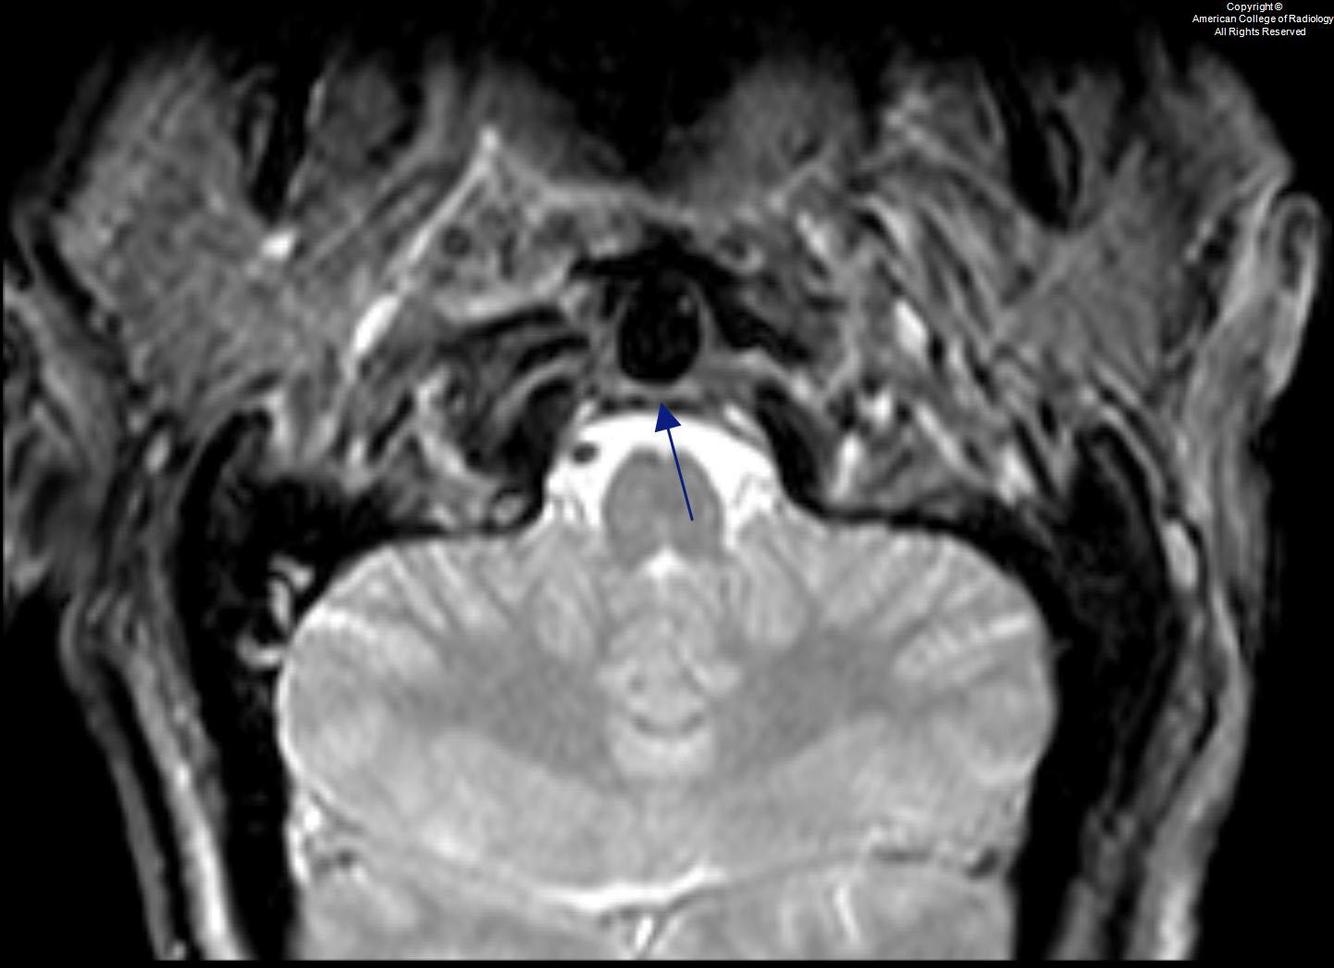

L5/S1 spondylolytic spondylolisthesis with severe bilateral L5/S1 neuroforaminal stenosis and severe bilateral L5 nerve root impingement.